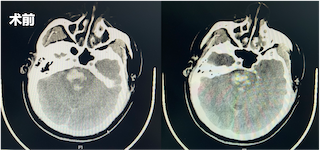

术后第一天,患者仍为浅昏迷状态,但在刺激下可见患者四肢收缩,复查头部CT发现脑干血肿较前明显减少。经神经内科重症监护室医护人员为其制定了专业的诊疗计划,随后团队成员持续术后关注,并向穿刺引流管中注射溶解血肿块的药物。随后,患者逐渐有了意识,对于外界的呼唤有了反应,对外界的刺激产生了回应。

术后一周再次复查CT显示脑干中的血肿明显较前减少。直至三周后,再次复查CT,患者已经没有血肿块,意识较前明显好转,遂转入普通病房继续治疗。在普通病房,患者还同时接受专业的康复训练和中医针灸治疗,患者四肢活动较前好转,目前,已出院至康复医院继续进行康复训练。